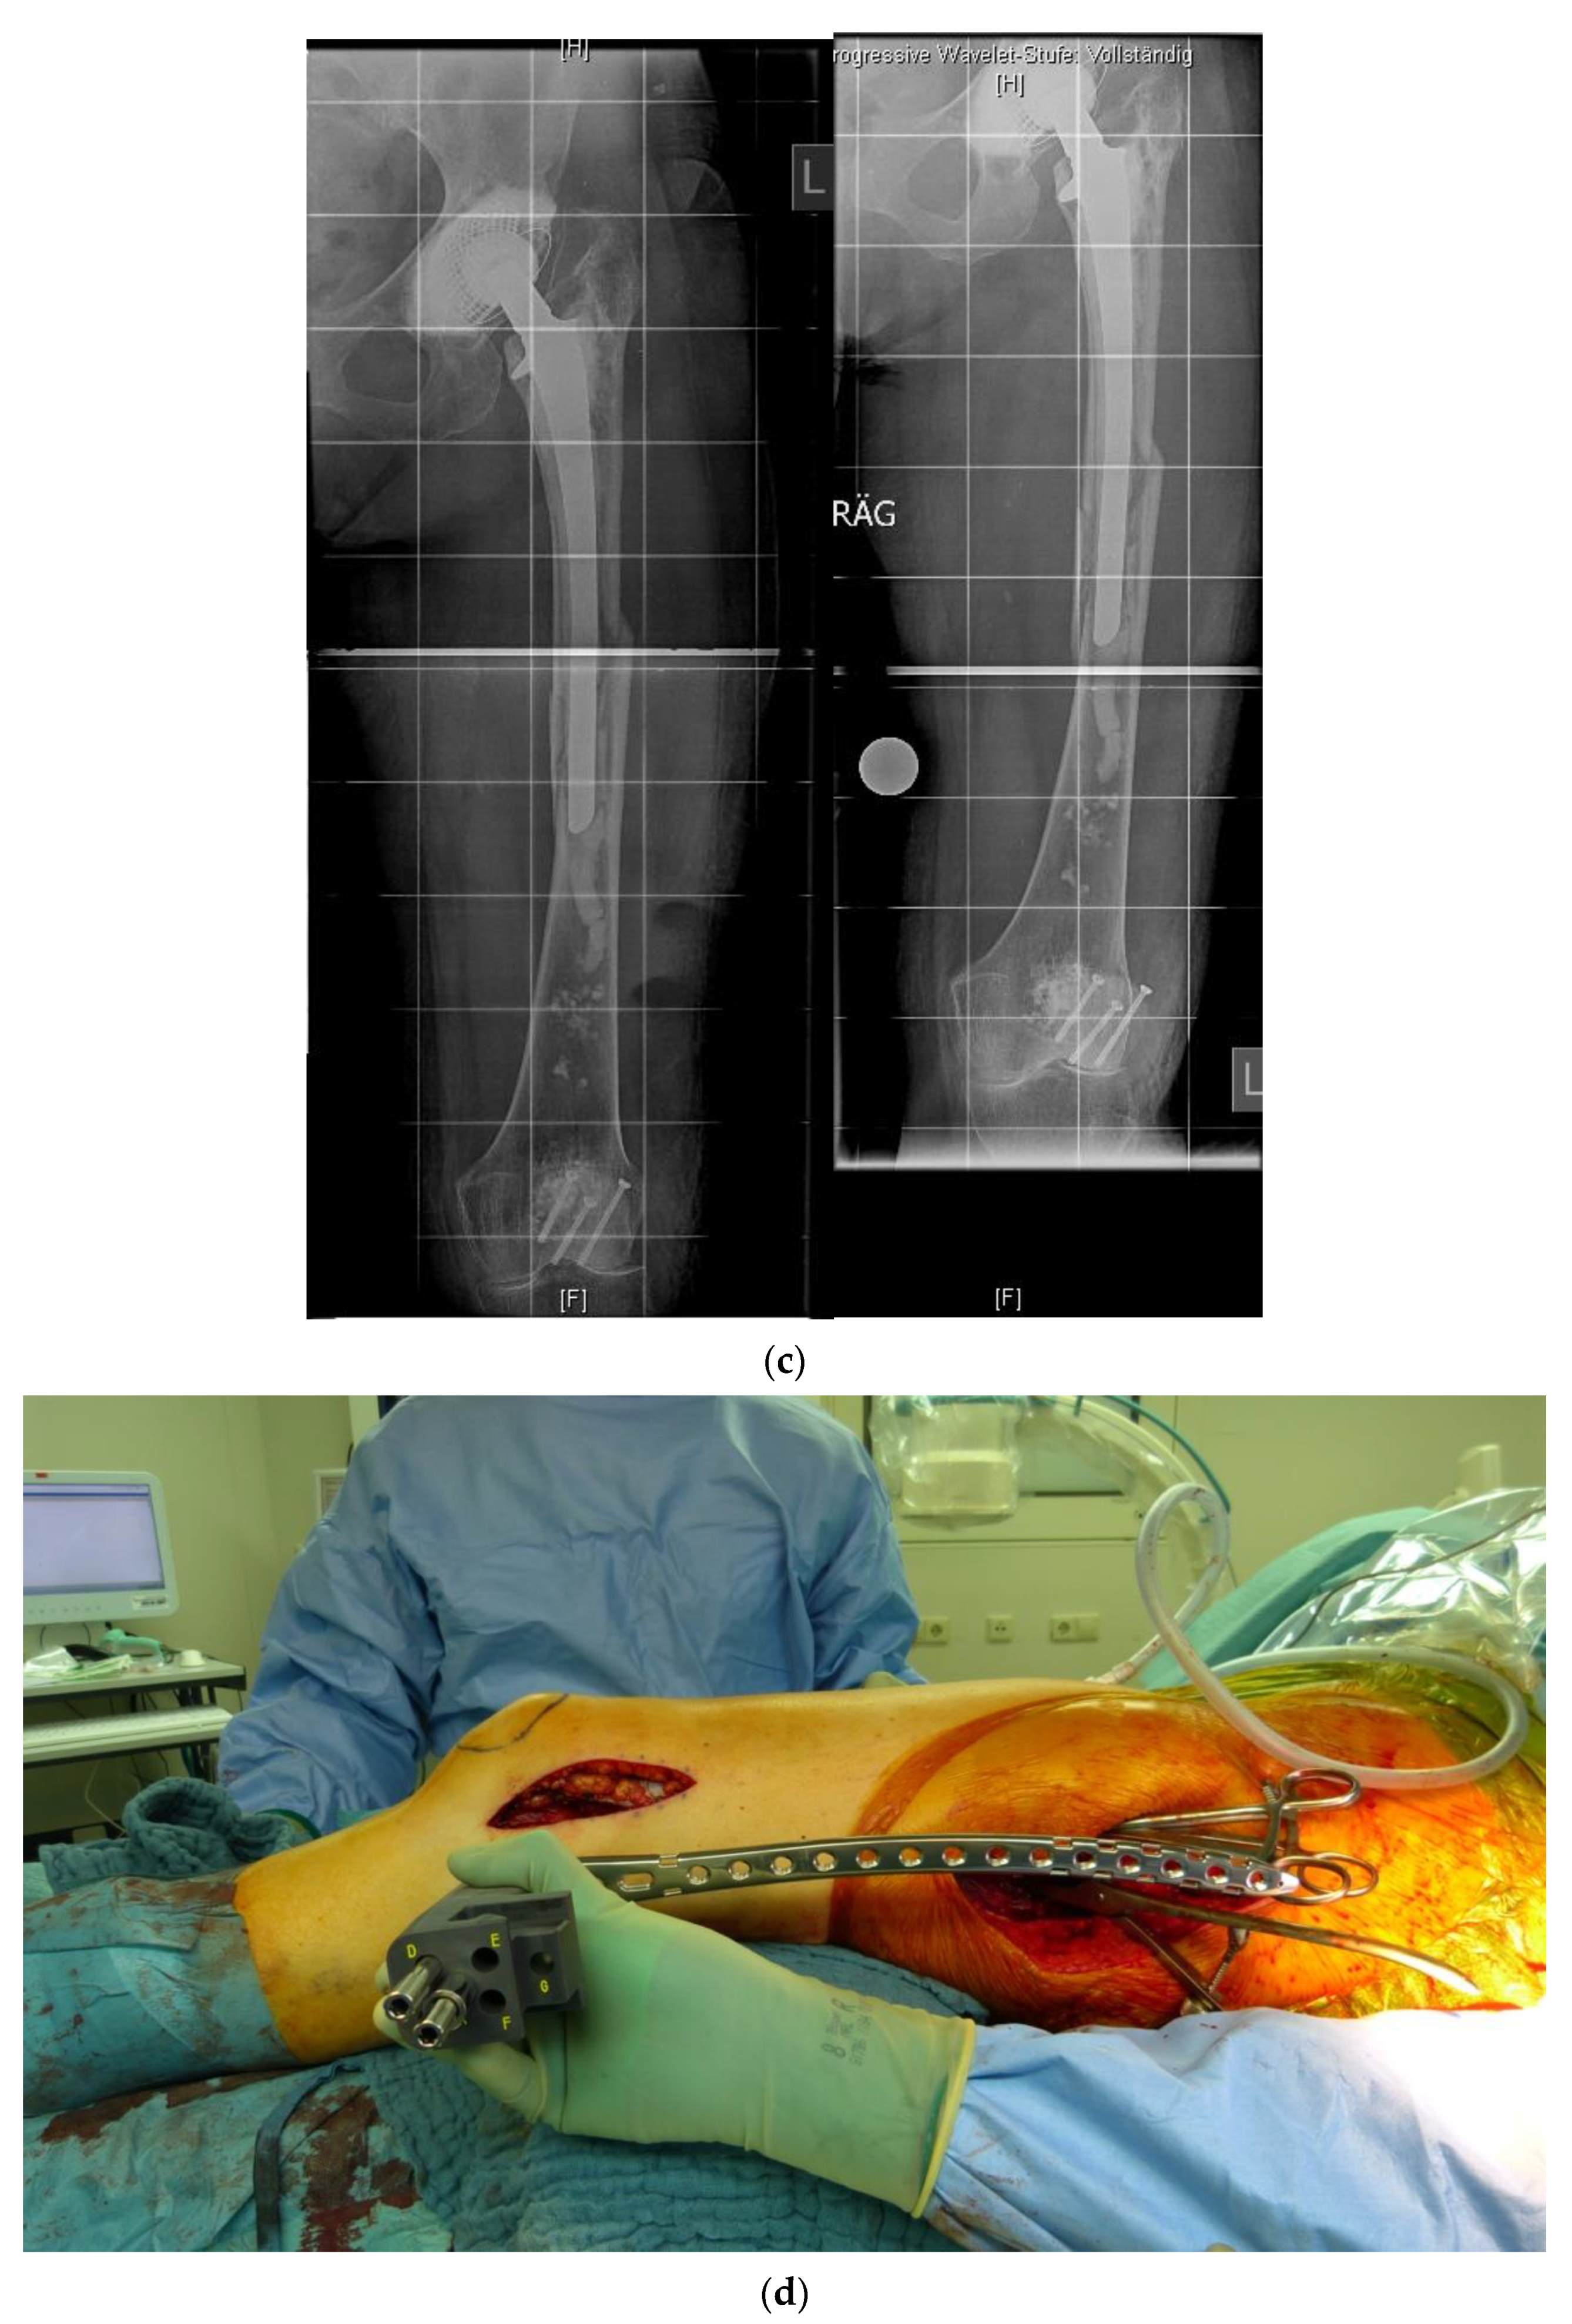

In revision cases and interprosthetic fractures, double plating is an alternative treatment option to avoid high-risk operations such as a total femur replacement. Figure 4 shows a successfully treated hypertrophic non-union after several interprosthetic re-fractures, using double plating in combination with autologous bone-grafting and growth factor application.

Figure 4. (a) Interprosthetic hypertrophic non-union. Intraoperative situs showing the failed plate fixation and the non-union. (b) Intraoperative situs showing the double plating. (c) Double plating combined with bone-grafting and growth factor application. (d) Postoperative follow-up X-rays after 6 weeks, 12, and 24 months, demonstrating complete healing and remodeling of the fracture.